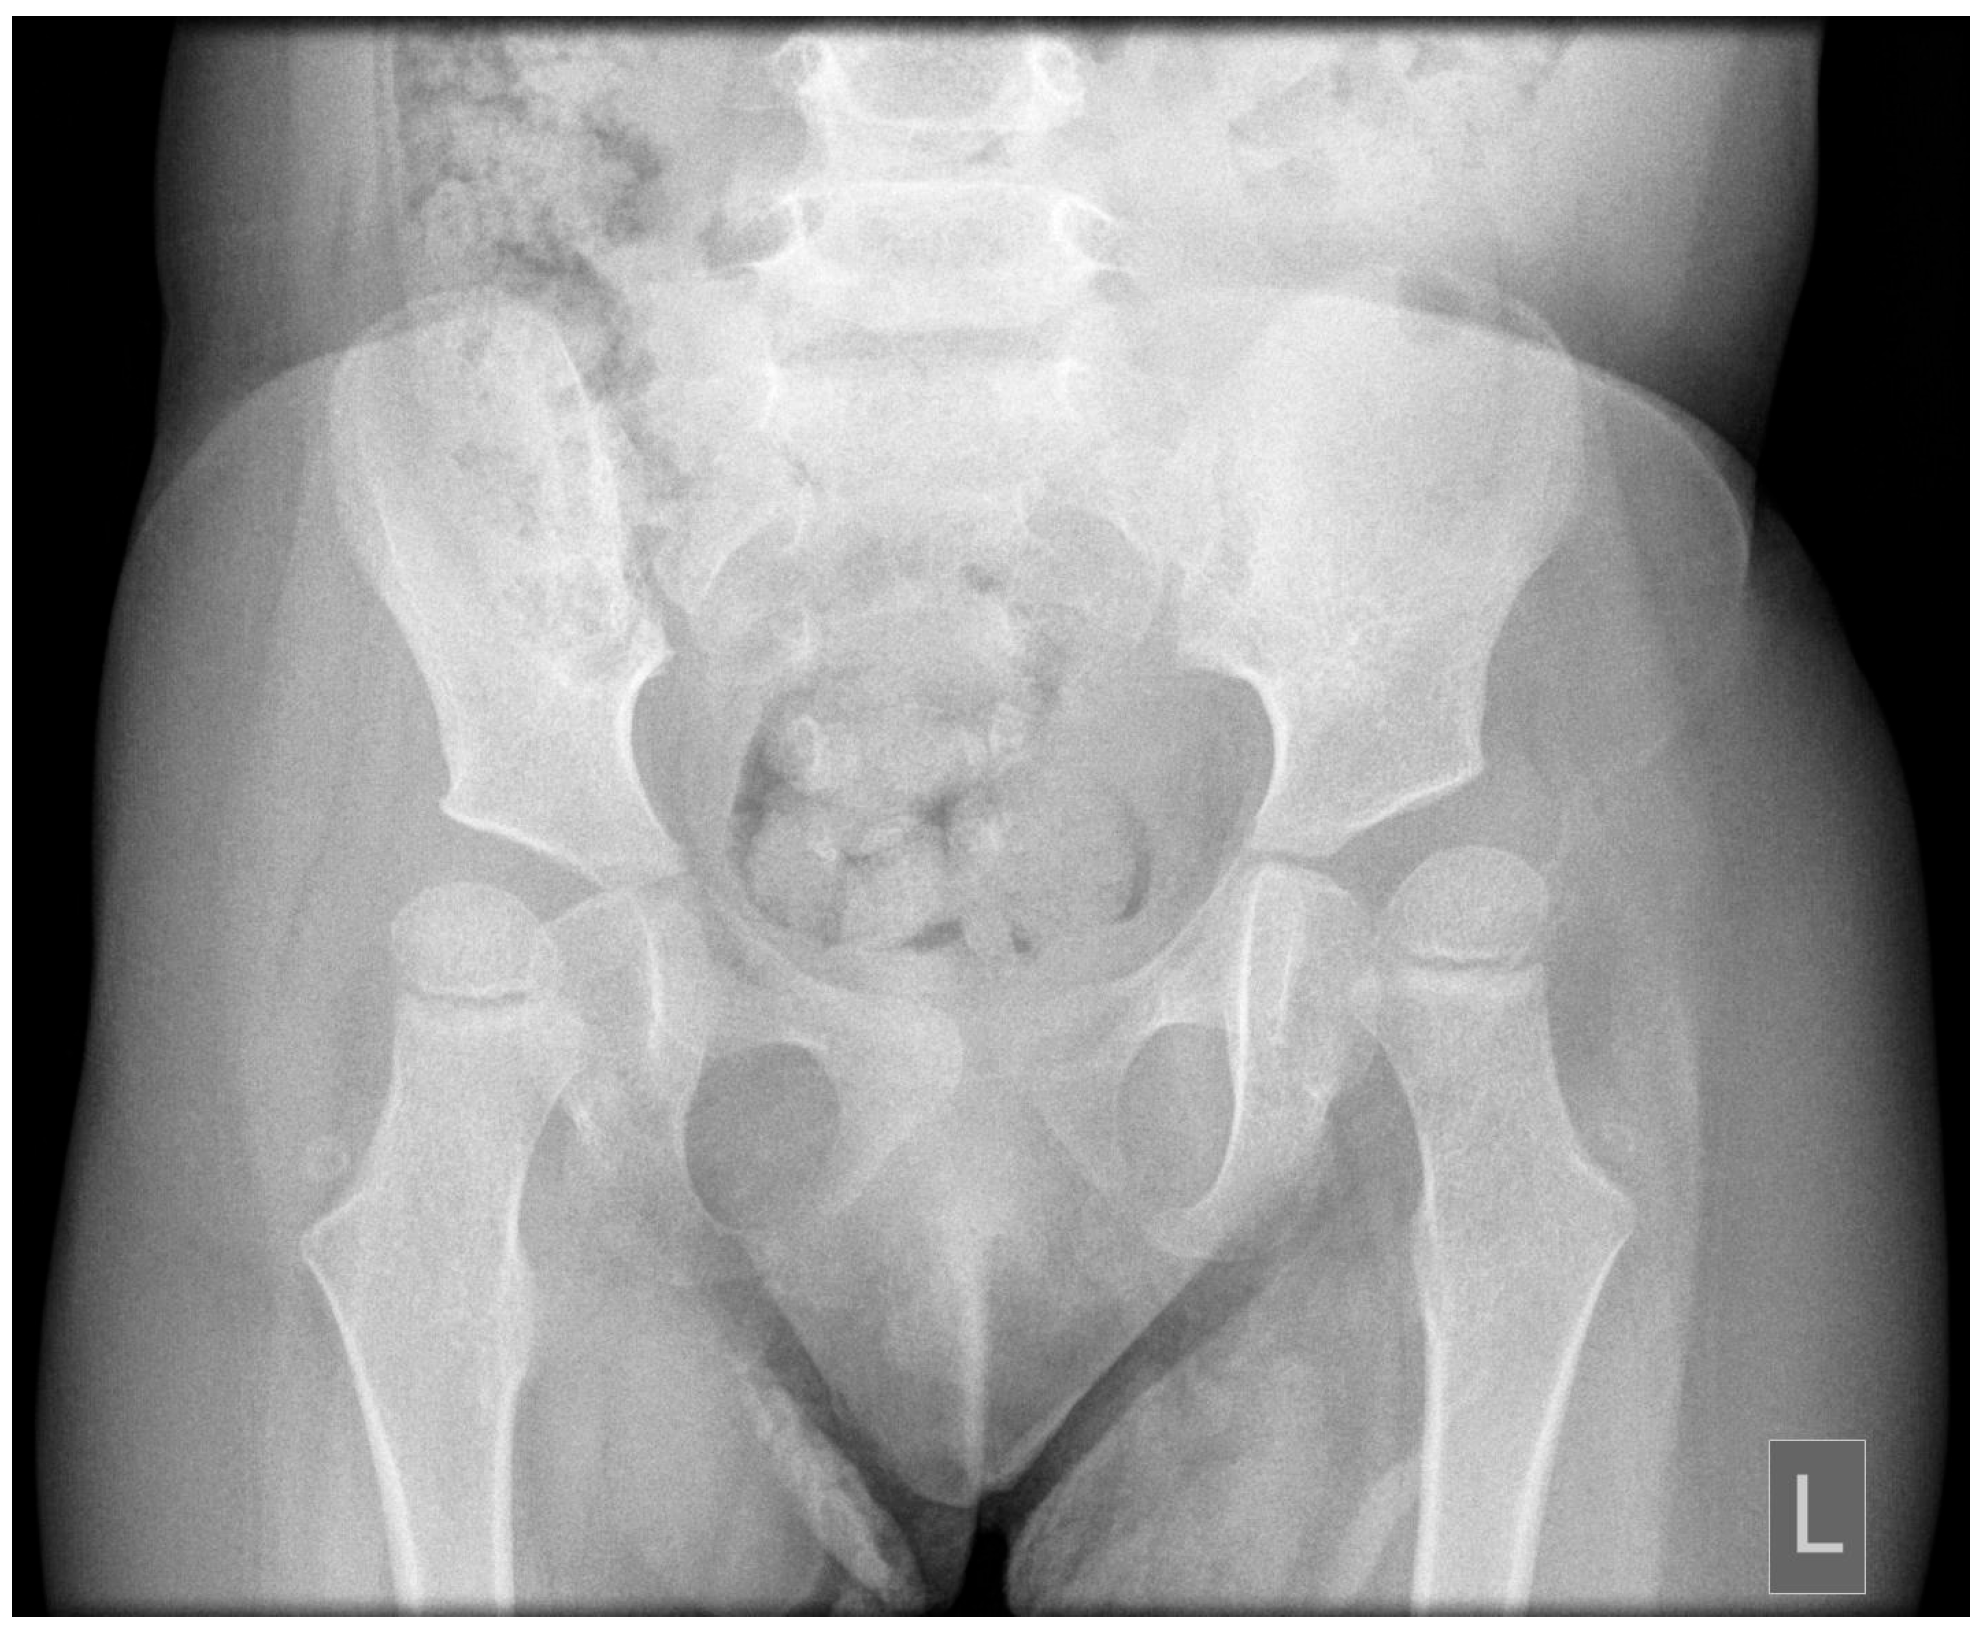

Postnatal brain MRI confirmed the diagnosis of JS based on the presence of the molar tooth sign (Figure 1). Polysomnography performed at 1 year of age demonstrated prolonged sleep latency (112 min), moderate mixed sleep apnea (AHI 5.4/h), and significant oxygen desaturation with a nadir SpO2 of 77%. Ophthalmologic follow-up confirmed persistent bilateral hyperopia with astigmatism requiring optical correction, consistent with cerebellar-related visual instability. Pelvic radiography performed at 2.5 years of age revealed asymmetric lateral migration of the femoral heads, more pronounced on the left side, with reduced acetabular coverage consistent with early subluxation (Figure 2). Clinically, the left lower limb presented with persistent adduction positioning. Diagnostic findings demonstrated cerebellar and brainstem abnormalities with direct functional implications for postural control, respiratory regulation, and motor development (Table 1).

Figure 2. Pelvic radiograph demonstrating asymmetric lateral migration of the femoral heads, more pronounced on the left side, consistent with early hip displacement.